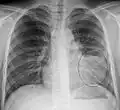

Normal AP CXR

-

Normal lateral CXR -

AP CXR showing left lower lobe pneumonia associated with a small left sided pleural effusion -

AP CXR showing right lower lobe pneumonia -

AP CXR showing pneumonia of the lingula of the left lung -

Right upper lobe pneumonia as marked by the circle. -

Left upper lobe pneumonia with a small pleural effusion.

Right lower lobe pneumonia as seen on a lateral CXR